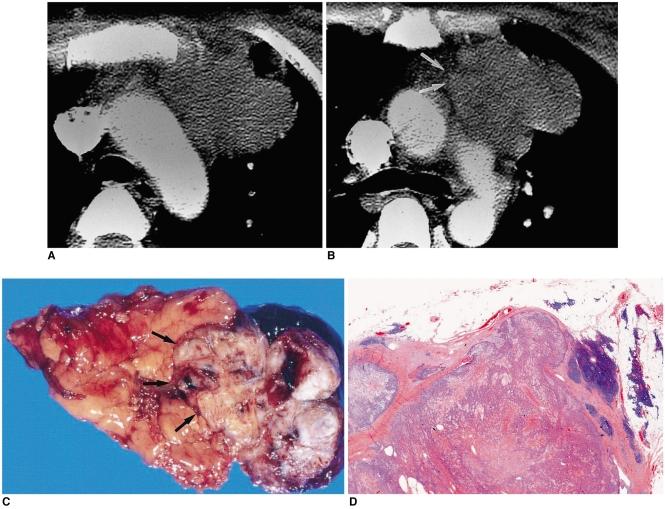

Thymic epithelial tumor is a distinctive pathologic entity exhibiting variable histologic features and heterogeneous oncologic behavior. Among the various classification systems, that of the World Health Organization has been adopted because of good correlation between histologic appearance and oncologic behavior. Radiologically, a smooth contour and round shape are most suggestive of a type-A tumor, whereas an irregular contour most strongly suggests type C. Pleural seeding is rare in type-A and AB tumors; calcification is suggestive of type B. Type-C tumors are significantly larger and more commonly associated with lymphadenopathy than type B3. At T2-weighted MR imaging, lobular internal architecture is more prominent in types B1, B2, and B3 tumors than in others. However, imaging findings among the various types overlap to some extent, and the ability of imaging studies to differentiate types AB, B1, B2, and B3 is limited.